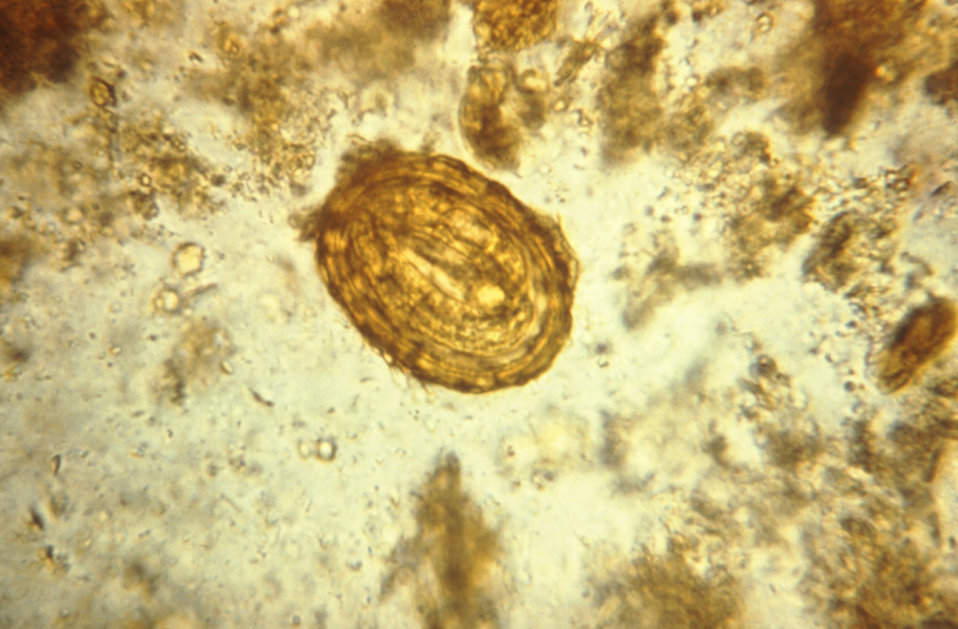

Стул со слизью у собаки, вызванный паразитами, диагностируют с помощью анализа кала, позволяющего найти яйца гельминтов и некоторых простейших.

Стоит отметить, что яйца гельминтов выходят не с каждым актом дефекации.

Чтобы результат был точным, сдавать анализы рекомендуется несколько дней. Для обнаружения простейших кал доставляют в лабораторию как можно раньше. Ведь эти паразиты способны погибнуть уже через 30 минут после акта дефекации, и лаборанты ничего не смогут обнаружить.

Микроскопическое исследование кала позволит выявить распространенных кишечных паразитов, в то время как цитология и тест на лямблии помогут найти менее распространенных паразитов. Если эти тесты отрицательны и нет признаков неблагоразумия в питании, стресса или травмы, будут изучены более хронические причины воспаления.

При микроскопическом исследовании в кале можно выявить детрит, остатки пищевых веществ, элементы слизистой оболочки кишечника, клеточные элементы: лейкоциты, эритроциты, макрофаги, опухолевые клетки, кристаллы, яйца гельминтов, паразитирующие в кишечнике простейшие, микроорганизмы. Данные микроскопического исследования могут дать представление о состоянии переваривающей способности кишечника, о состоянии слизистой оболочки (главным образом толстого кишечника).